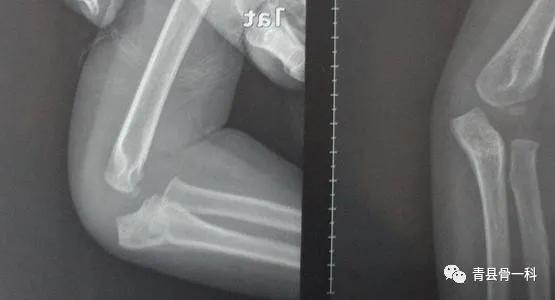

儿童骨折的特点:1、儿童骨血液较丰富,矿物质、纤维组织量多,多出现青枝骨折、皱褶骨折和弯曲骨折;2、儿童的骨膜较厚,矿物质较多,少有粉碎性骨折,若移位明显,张力侧骨膜断裂,另一侧也相对完整,这有利于复位后的稳定及愈合,儿童骨骺损伤则相对严重;3、儿童软骨在X光片不显影,故损伤后要查CT或MRI。

如何简单的判断儿童骨折,首先要向患儿或其家长询问受伤史及肿处局部的情况,比如肿胀、疼痛、压痛、瘀斑,以及是否有明显的有畸形、骨擦音。以上能一目了然可以判断,当然,要借助X光片,必要时还要增加CT或MRI。

儿童骨折常规的处理方法,有手法复位、小夹板固定、石膏固定,皮肤牵引、骨牵引、闭合复位,克氏针固定、弹性钉固定或者外固定架固定,必要的时候切开复位内固定。

在儿童发生骨折以后,可能会出现骨折部位的剧烈疼痛肿胀以及淤青,如果孩子比较小,无法通过语言表达自己的身体状况,家长需要及时送孩子去医院进行影像学检查。儿童骨折常常发生青枝骨折,因此愈合时间也比较短。但是由于孩子年纪小,可能会出现一些固定的问题,需要家长多加看护。